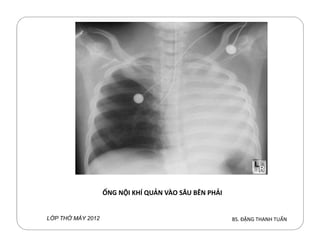

Ống NKQ vào sâu:

Thường vào sâu bên (P), phổi (T) bị xẹp

Cách phát hiện:

Phần cn lại NKQ bên ngoài: ngắnPhần cn lại NKQ bên ngoài: ngắn

Triệu chứng xẹp phổi (T)

X quang ngực: xẹp phổi (T) + ống NKQ vào sâu bên (P)

Xử trí: rút bớt NKQ ra

Phim X quang ngực thường: dễ

Phim ỹ thuật số: hó ước lượng chiều dài

ỐNG NỘI KHÍ QUẢN VÀO SÂU BÊN PHẢI